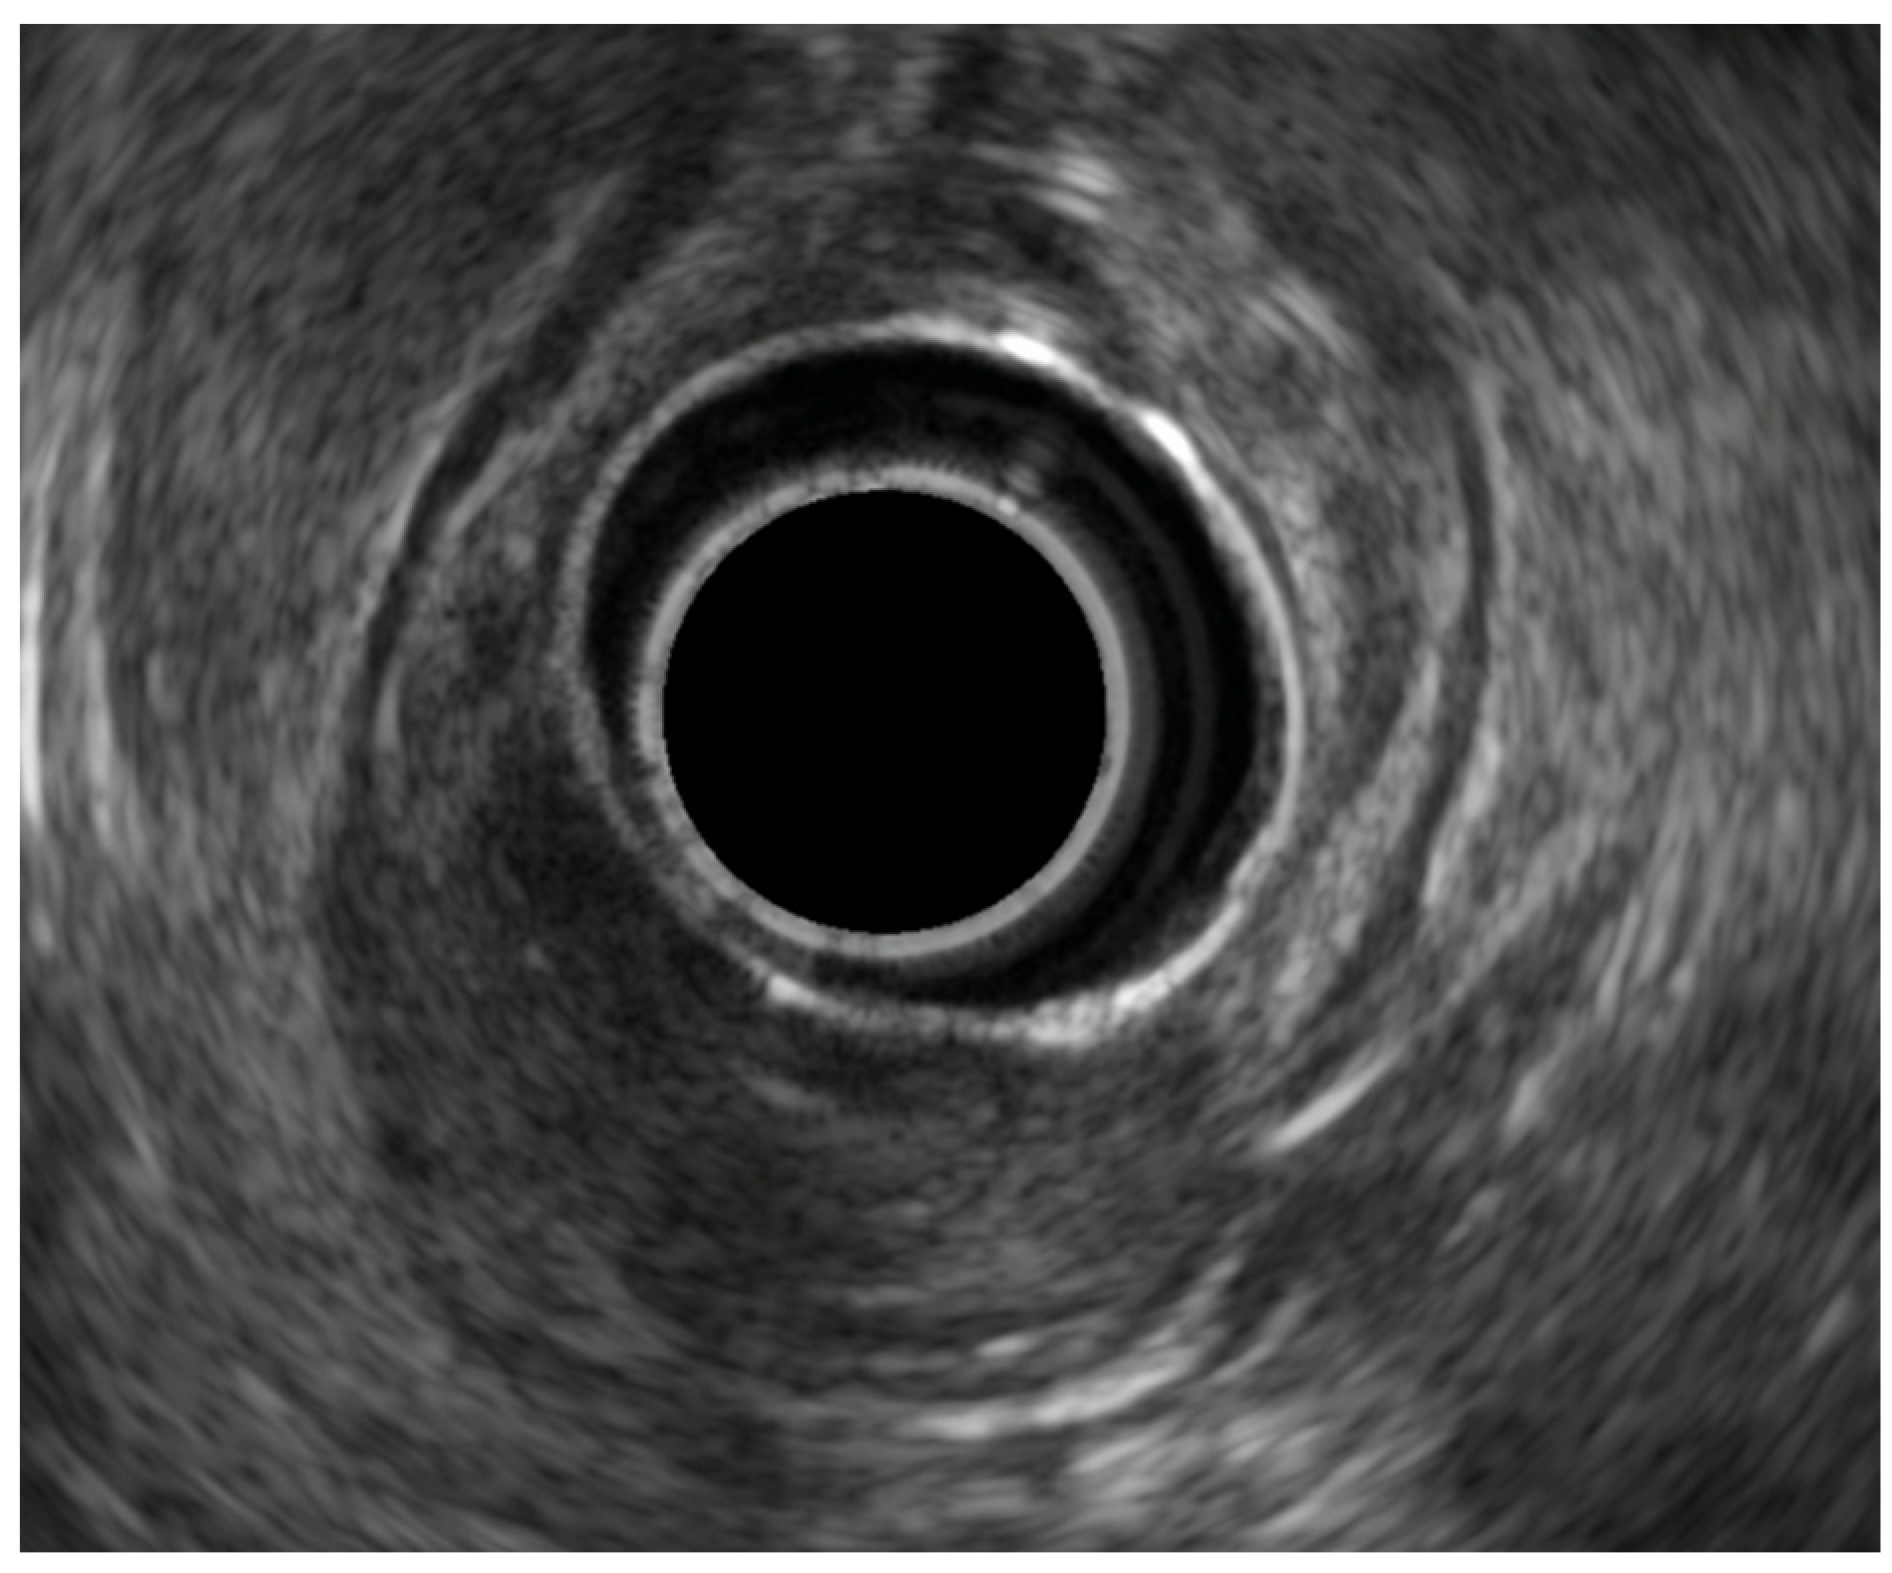

7. Endoscopic Rectal Ultrasound

8. Rectal Neoplastic Lesions

8.1. Rectal Superficial Cancer

8.2. Advanced Rectal Cancer